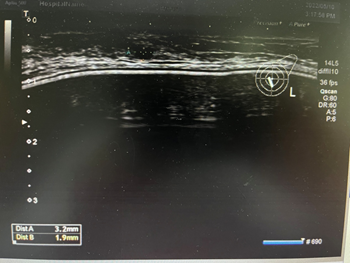

形态较规整,但内部还是不均匀,BI-RADS  4a类